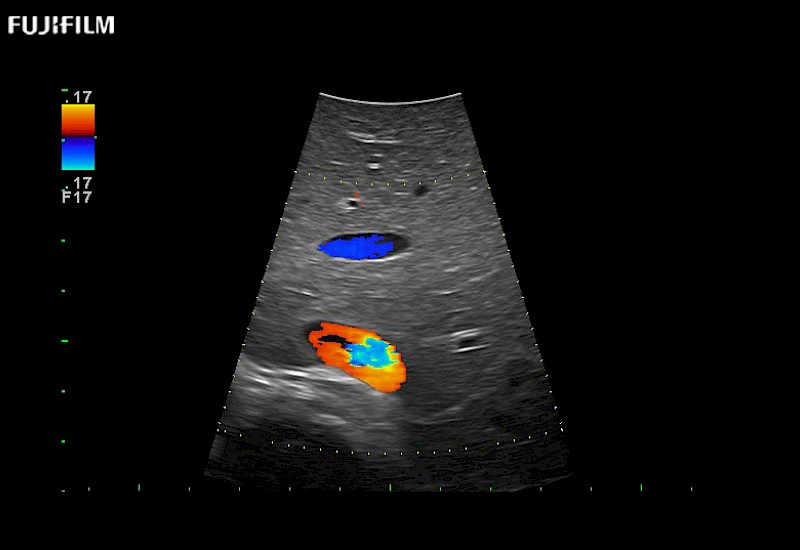

for use during general and laparoscopic procedures: Tumor localization & staging, Ablation, Resection, Biopsy, Transplant, Abdominal exploration, Robotic surgery

Our dedication to Laparoscopic Surgery allows us to offer superior image quality, outstanding system reliability and intuitive use of cutting edge technology.